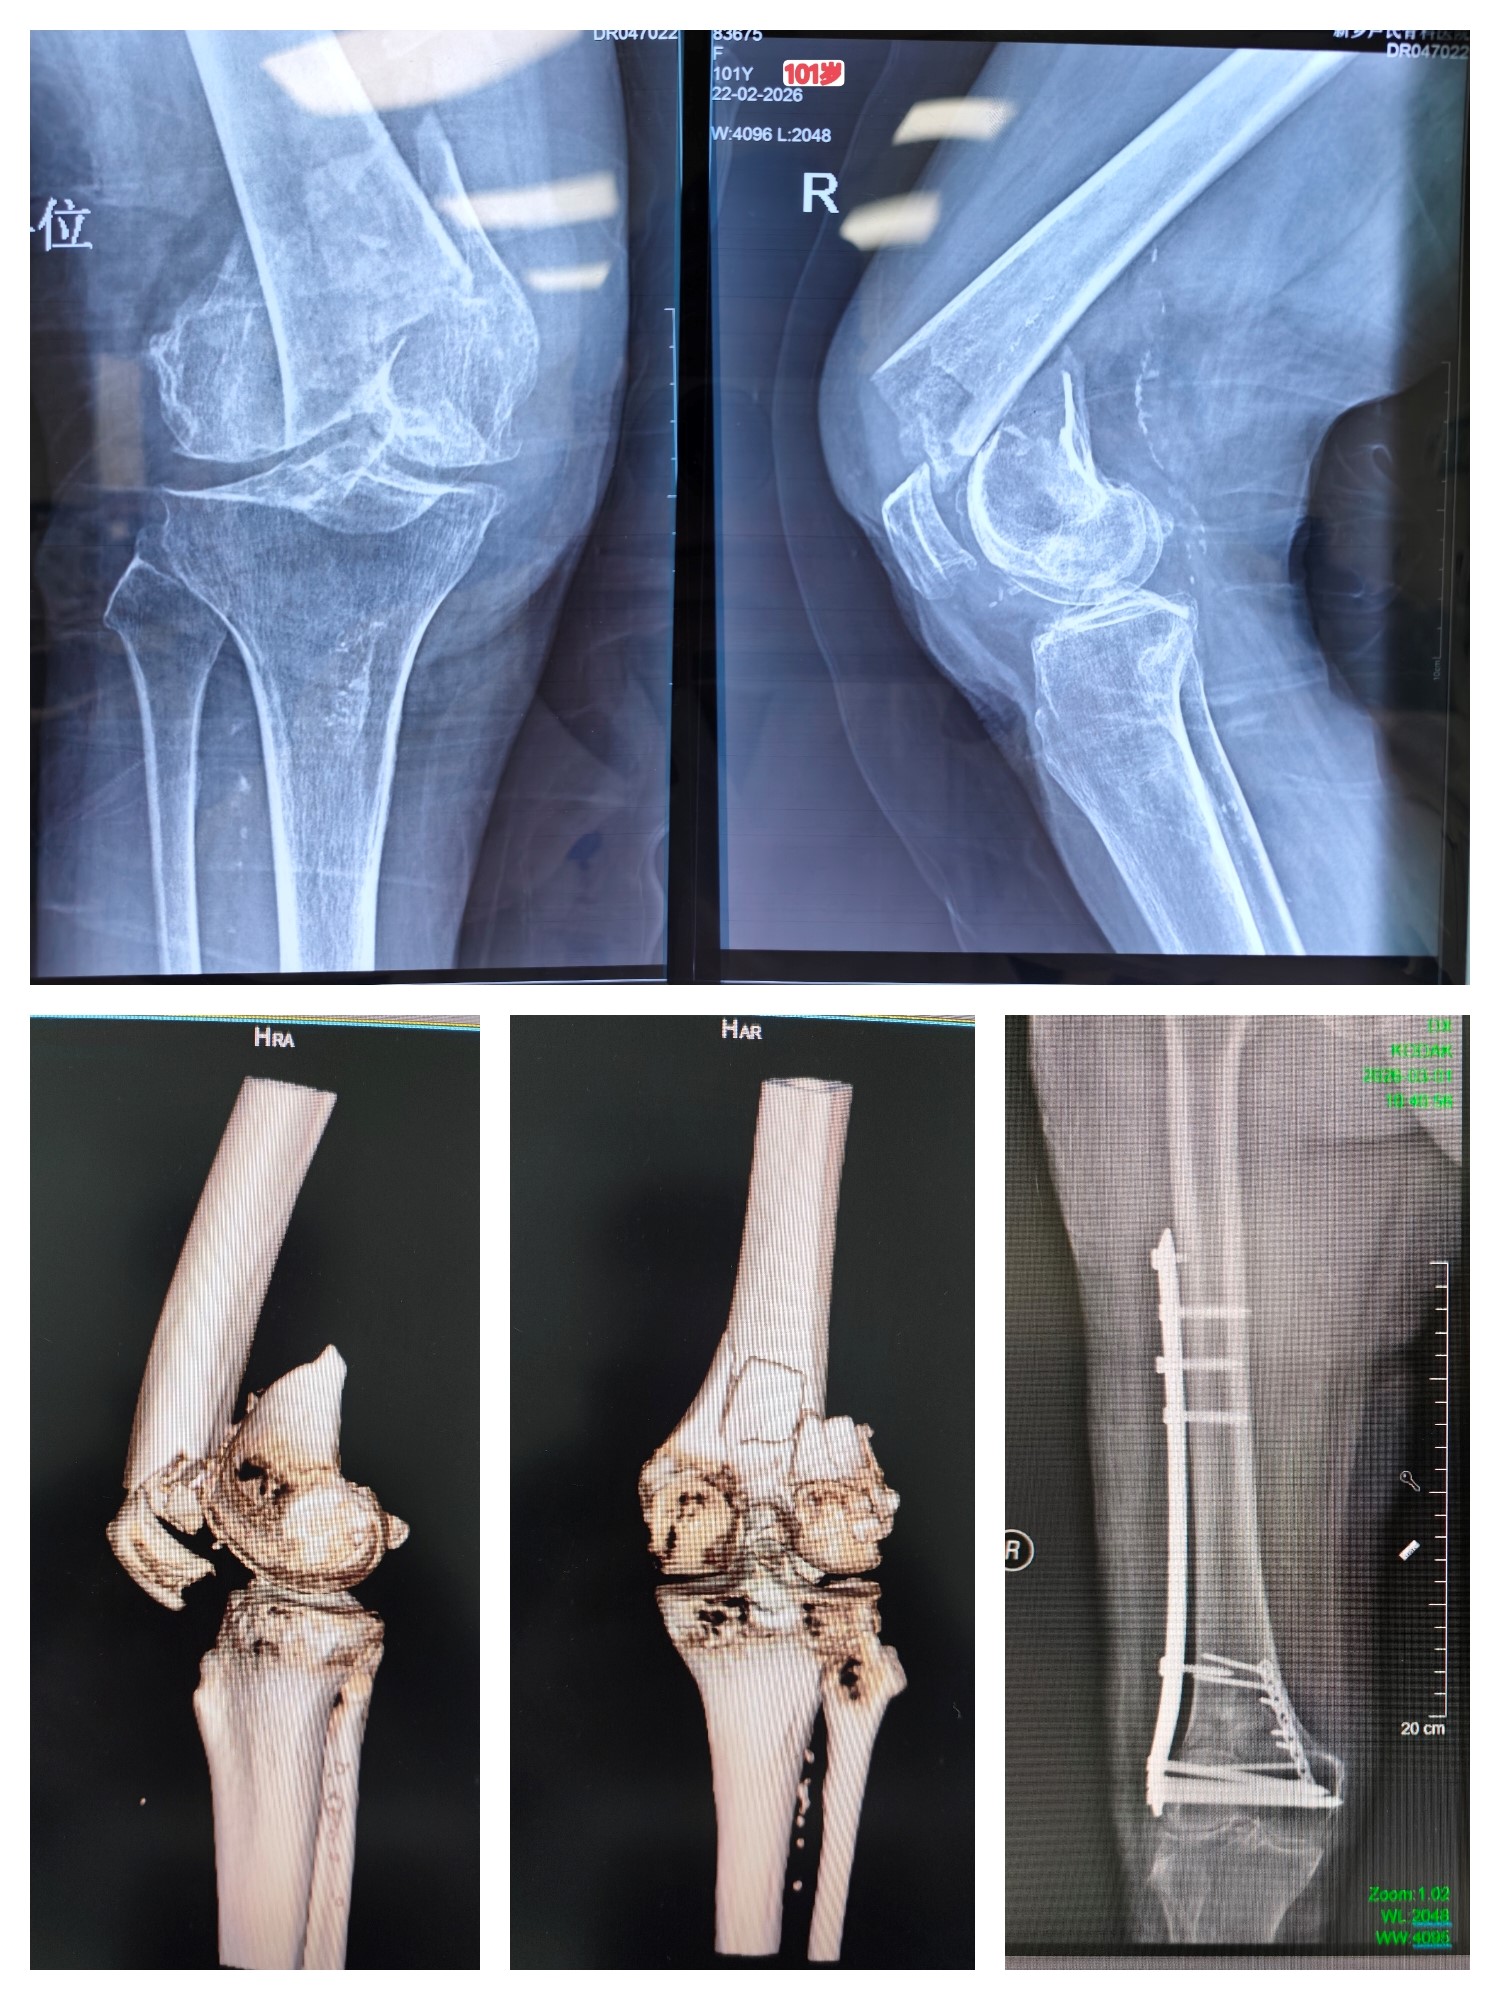

近日,我院郑州院区创伤急救中心成功为一位101岁高龄的股骨远端骨折患者实施手术,再次彰显了我院强大的综合救治能力与多学科协作优势。

患者已百岁高龄,疼痛难忍,且围手术期麻醉风险极高,家属辗转多院后慕名而来。创伤急救中心马献忠主任接诊后认为:高龄不是手术禁区,但需要更精细的围术期管理,马主任立即启动MDT多学科会诊,重症医学科徐道志主任、麻醉科于国军主任、护理团队、影像科、超声医学中心、康复科进行多学科会诊,全面评估风险,精心制定方案。手术由于国军主任实施麻醉保障,马献忠主任主刀,团队密切配合,手术全程耗时不足一小时,顺利完成。